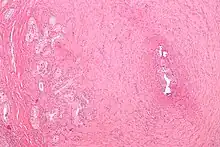

| Micrograph of vasitis nodosa (left of image). H&E stain. | |

Vasitis nodosa is a complication experienced in approximately 66% of men who undergo vasectomy.[1] It is a benign nodular thickening of the vas deferens, in which small offshoots proliferate, infiltrating surrounding tissue.[2] It can be mistaken for low-grade adenocarcinoma by pathologists,[3] and is implicated in late vasectomy failure.[2]